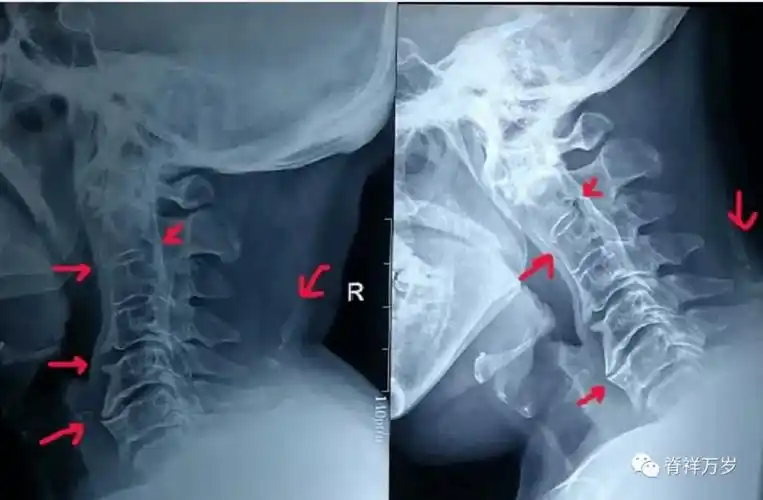

严重的异状颈椎 手法小心